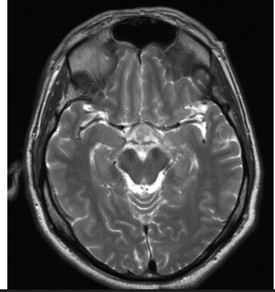

Computed tomography (CT) of the head demonstrated a poorly defined hypodense lesion in the medial temporal lobe with mild enlargement of the pituitary gland. Subsequent magnetic resonance imaging (MRI) of the brain revealed an enhancing lesion involving the pituitary gland with extension into the sella as well as suprasellar and infrasellar regions, including involvement of the optic chiasm (Figure 2). Given concern for disseminated disease, CT imaging of the chest was obtained and demonstrated scattered bilateral pulmonary densities with a focal rounded infiltrate in the right lower lobe (Figure 3).

The patient was initiated on liposomal amphotericin B; however, therapy was discontinued after two weeks due to the development of acute kidney injury. During the two-week interval, he demonstrated marked clinical improvement with a resolution of headaches and improvement in visual and urinary symptoms. Repeat MRI showed a significant decrease in the size of the enhancing sellar lesion with a complete resolution of previously noted infra- and supratentorial foci, consistent with treatment response (Figure 4). He was transitioned to oral voriconazole for long-term antifungal therapy.